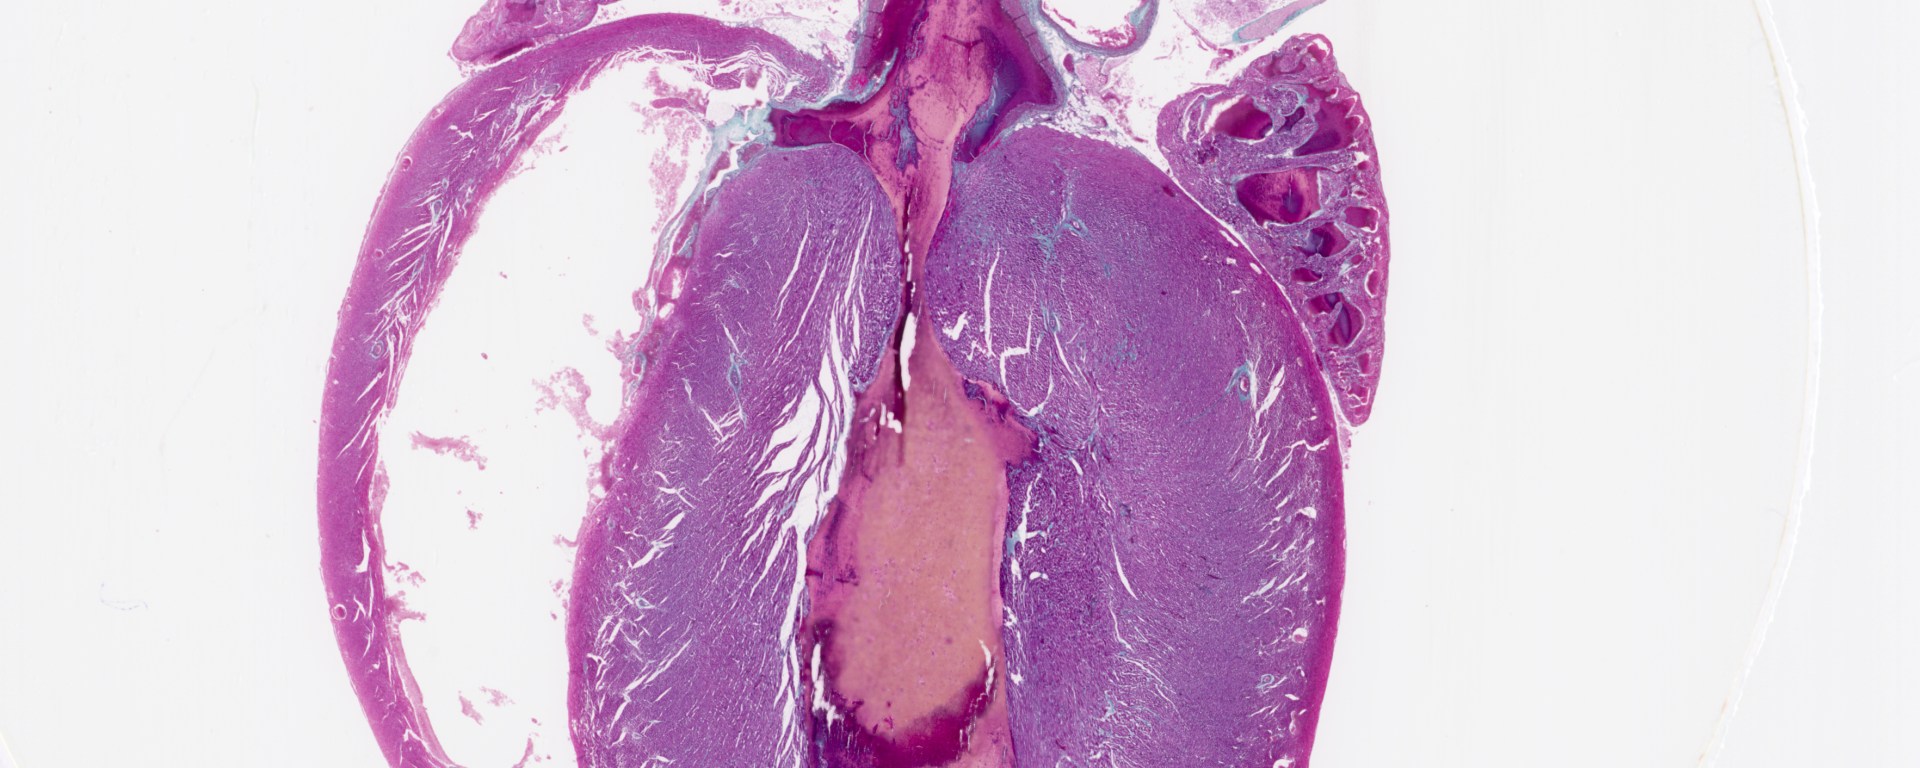

Images Whole Rat Heart, l.s. Whole rat heart, l.s. (TM: ~2.5x, picture taken with a Nikon Coolscan V slide scanner) Share this: Email a link to a friend (Opens in new window) Email Share on X (Opens in new window) X Share on Facebook (Opens in new window) Facebook Like Loading...